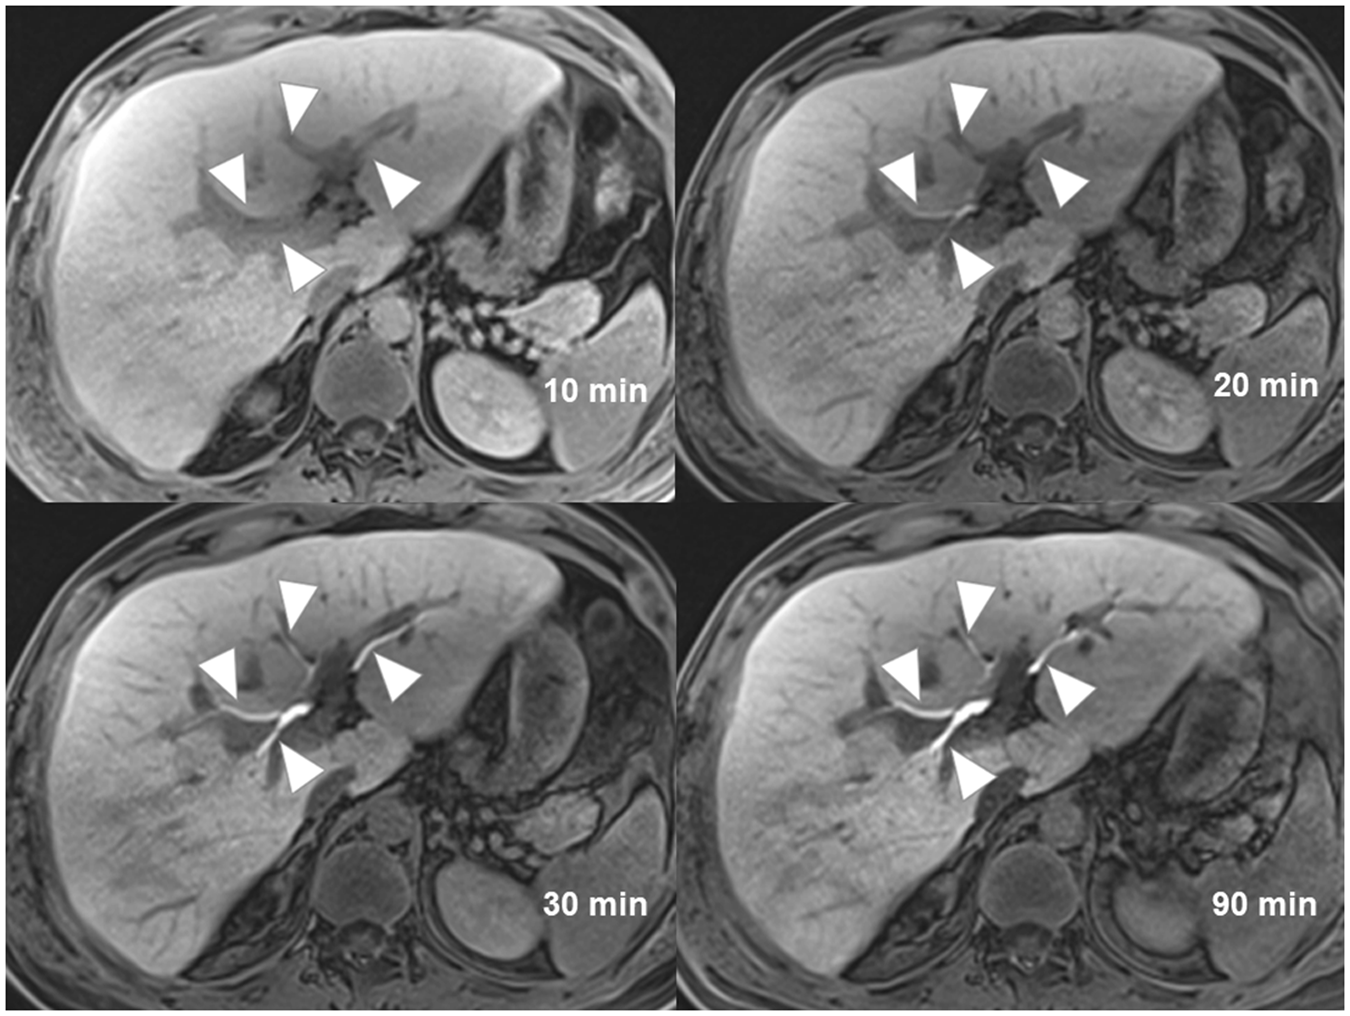

Figure 1

A 36-year-old man with liver injury (not shown). Images of contrast enhanced MR cholangiography acquired at 10 minutes, 20 minutes, 30 minutes and 90 minutes show progressive improvement of intrahepatic bile ducts visualization (arrowheads) from very poor visualization at 10 minutes to excellent visualization at 90 minutes. The average scores given by three readers are 1.00 (10 minutes), 4.00 (20 minutes), 4.67 (30 minutes), 5.00 (90 minutes).